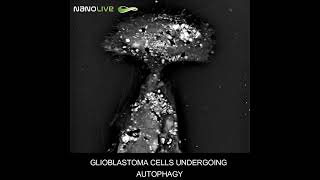

11.3 Basal autophagy marked by GFP-LC3 in single LCC9 cells (Real-time) Glioblastoma cells undergoing autophagy

Glioblastoma cells undergoing autophagy Movie 20 Time-lapse microscopy of autophagy a single MCF7 cell

Microinjection Dextran Red and GFP mRNA into MCF7 cells on Etaluma LS720 by Zambon Lab at KGI Glioblastoma cells undergoing autophagy observed with holo-tomographic microscope

Glioblastoma cells undergoing autophagy observed with holo-tomographic microscope Minimum fasting length required for autophagy | Guido Kroemer

11.3 Basal autophagy marked by GFP-LC3 in single LCC9 cells (Real-time) Glioblastoma cells undergoing autophagy

Glioblastoma cells undergoing autophagy Movie 20 Time-lapse microscopy of autophagy a single MCF7 cell

Microinjection Dextran Red and GFP mRNA into MCF7 cells on Etaluma LS720 by Zambon Lab at KGI Glioblastoma cells undergoing autophagy observed with holo-tomographic microscope

Glioblastoma cells undergoing autophagy observed with holo-tomographic microscope Minimum fasting length required for autophagy | Guido Kroemer